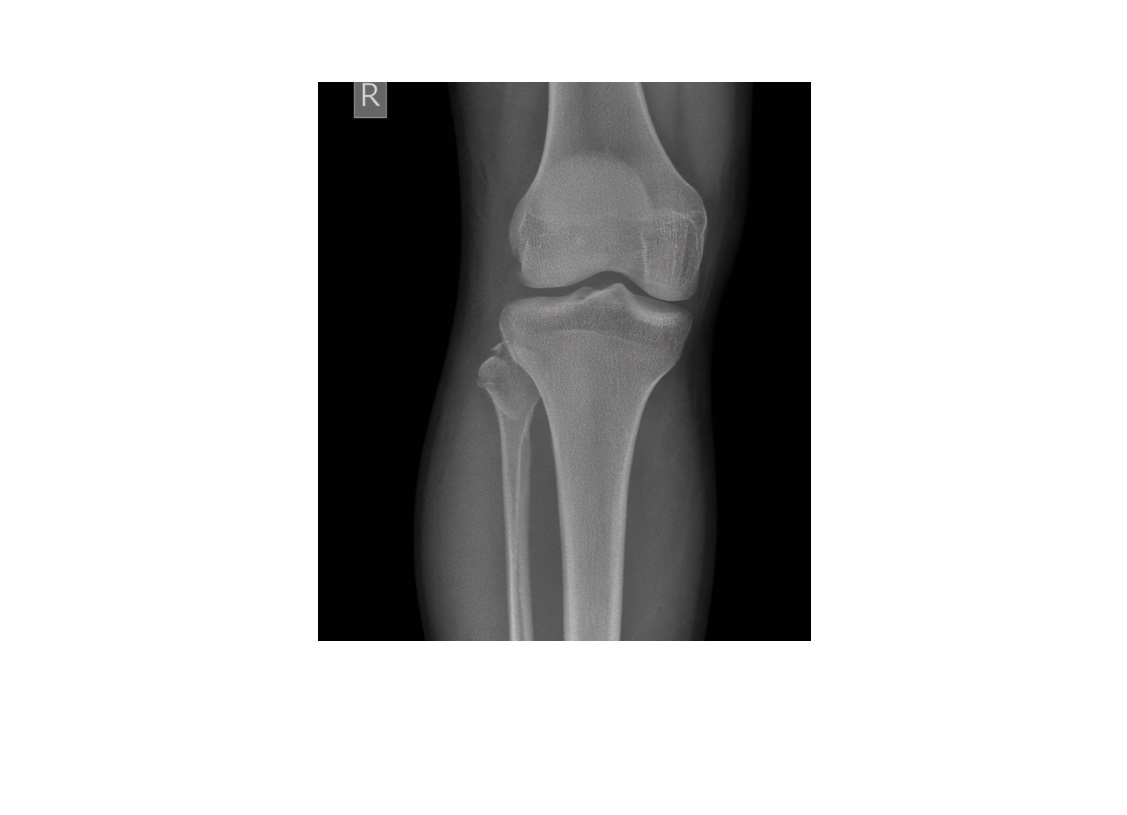

Segond fracture

Lateral tibial plateau

Associated with ACL tear (75%) and internal rotation

Reverse Segond fracture

Medial tibial plateau

Associated with PCL tear with external rotation. Associated with medial meniscus injury.

Arcuate sign

Avulsion of the proximal fibula

Associated with PCL tear